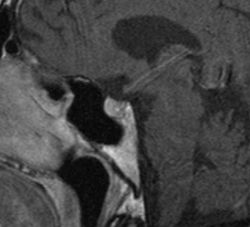

Transnasale Endoskopie

Mittels der vollendoskopischen transnasalen OP-Technik ist es möglich, Prozesse im Bereich der vorderen Schädelbasis und der Sellaregion minimalinvasiv zu versorgen. Hierzu gehören u.a. Hypophysenadenome, Kraniopharyngeome, Zysten und Meningeome. Der Vorteil der Technik liegt vor allem darin, dass die Endoskopie einen Rundumblick in der Tiefe gestattet. Dies ermöglicht die genaue Visualisierung von krankhaftem Gewebe auch in schwer zugänglichen Bereichen. In Koppelung mit der Neuronavigation können auch komplexe Pathologien präzise lokalisiert und adäquat therapiert werden.

MRT mit Nachweis eines großen zystischen Tumors, in diesem Falle ein sogenanntes Kraniopharyngeom.

MRT nach der Operation. Der Tumor konnte allein durch die Nase komplett entfernt werden.